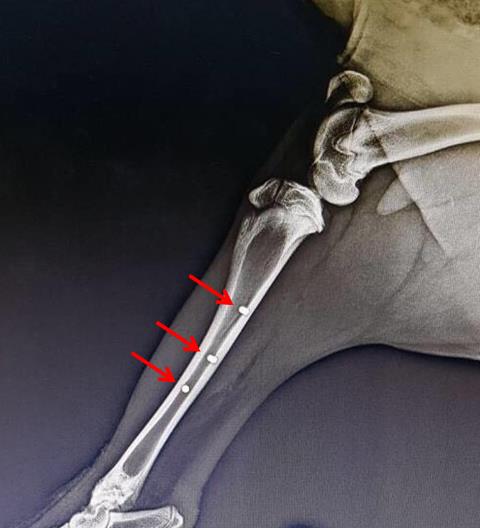

“We put the BIACOM® implants to tests according to the relevant ISO standards with excellent results, during which time the mechanical and fatigue properties and corrosion behaviour had been assessed. In cooperation with foreign and domestic partners (School of Dental Medicine in Zagreb, Institute of Genetic Engineering and Biotechnology in Gebze and Biomedical Research Center SAS), the biocompatibility in in-vitro conditions was evaluated, and preliminary in-vivo implantation tests were performed on large animal models,“ said Peter Krížik from the Institute of Materials and Machine Mechanics SAS.